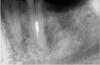

samsonov Опубликовано 30 июня, 2012 Поделиться Опубликовано 30 июня, 2012 Распломбировал премоляр... Ссылка на комментарий

ARislanV Опубликовано 1 июля, 2012 Автор Поделиться Опубликовано 1 июля, 2012 Распломбировал премоляр...Можете рассказать чем проходили, чем растворяли, сколько времени ушло? Ссылка на комментарий

samsonov Опубликовано 2 июля, 2012 Поделиться Опубликовано 2 июля, 2012 Можете рассказать чем проходили, чем растворяли, сколько времени ушло?Развёртки,ультразвук,лимонка,гипохлорит,2 посещения по 50-70 минут. Ссылка на комментарий